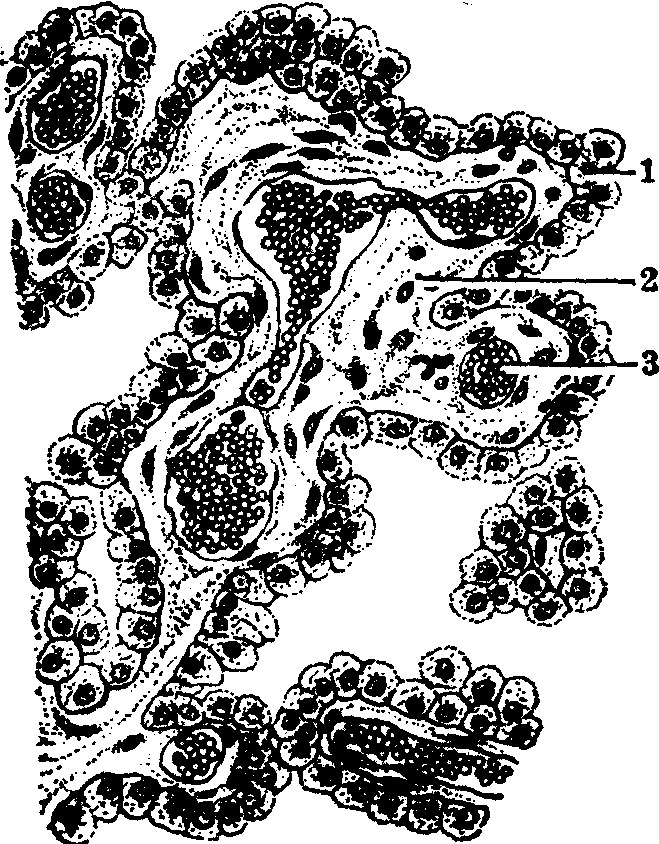

脉络丛位于脑室中,为含丰富血管的软膜结缔组织和被覆软膜内面的脉络丛上皮凸入脑室所成的褶。脉络丛表面粗糙,有许多不规则的突起和绒毛。胚胎发生时,第三脑室和第四脑室顶和侧脑室内侧壁很薄。这些部位的室管膜与外面富有血管的软膜紧连一起凸入脑室形成脉络丛(见图)。被覆脉络丛表面的室管膜特化为有分泌功能的上皮,称脉络丛上皮。

人第四脑室脉络丛

1.上皮 2.结缔组织 3.血管

组成脉络丛的结缔组织较疏松,含胶原纤维、成纤维细胞和巨噬细胞,并有丰富的血管,除小动脉和小静脉外,还有许多腔大的毛细血管(见图)。结缔组织中常见0.01~0.15mm大小的坚硬小体,称脑砂或砂瘤小体。此体呈圆形,为多层同心状的环层组成,随年龄增多,化学成分主要为碳酸钙、磷酸钙和磷酸镁,其作用还不了解。脉络丛是产生脑脊液的主要来源,由它的上皮以分泌方式所生。脑脊液量为80~100ml,为透明略有粘性的液体,含少许蛋白质,少量无机盐和葡萄糖,常见少数淋巴细胞。脑脊液不断更新,大部分经蛛网膜绒毛回流到颅内的静脉窦。中枢神经系浸泡于脑脊液中,能防止震动和机械性损伤,并对中枢神经系的物质代谢起重要作用.